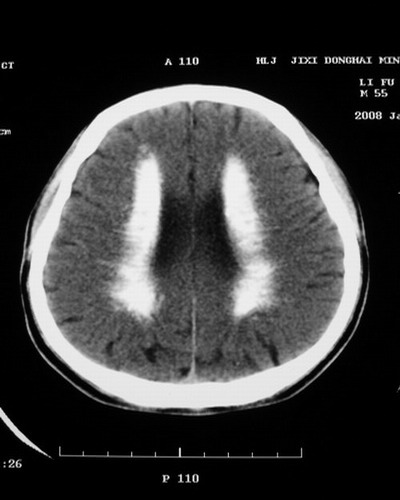

以下是引用随光逐影在2008-1-14 17:26:00的发言:[br]考虑为:甲状旁腺功能低下。需与fahr`s病相鉴别。建议:实验室检查。